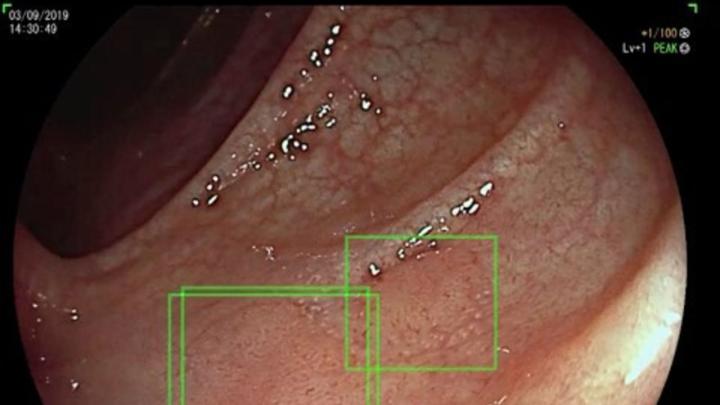

Algorytm bezpiecznej rekomendacji